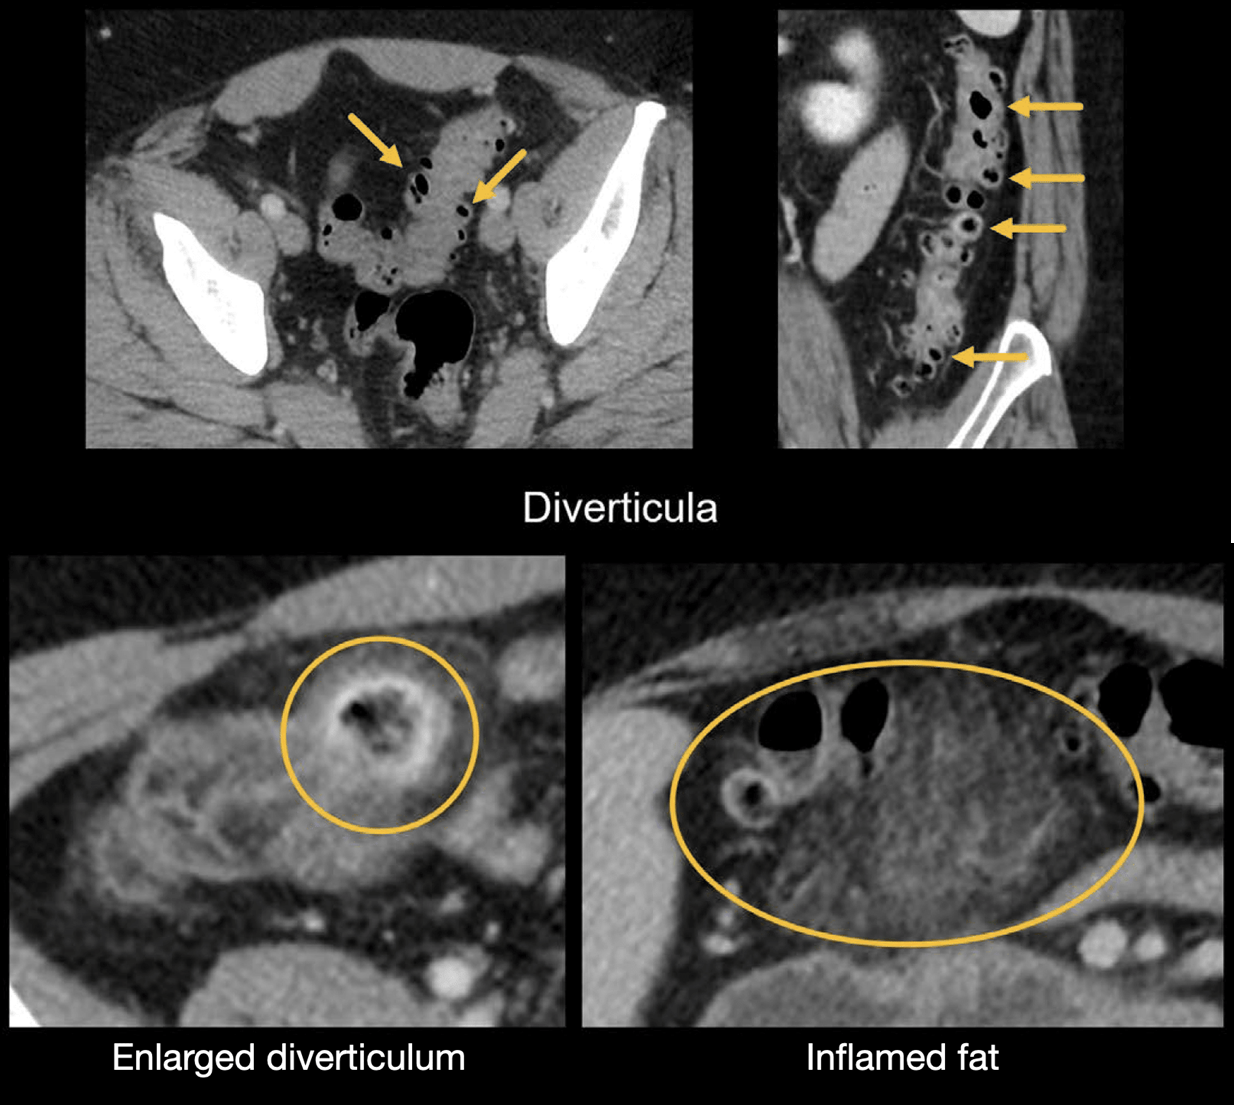

✔ CT 검사로 진단